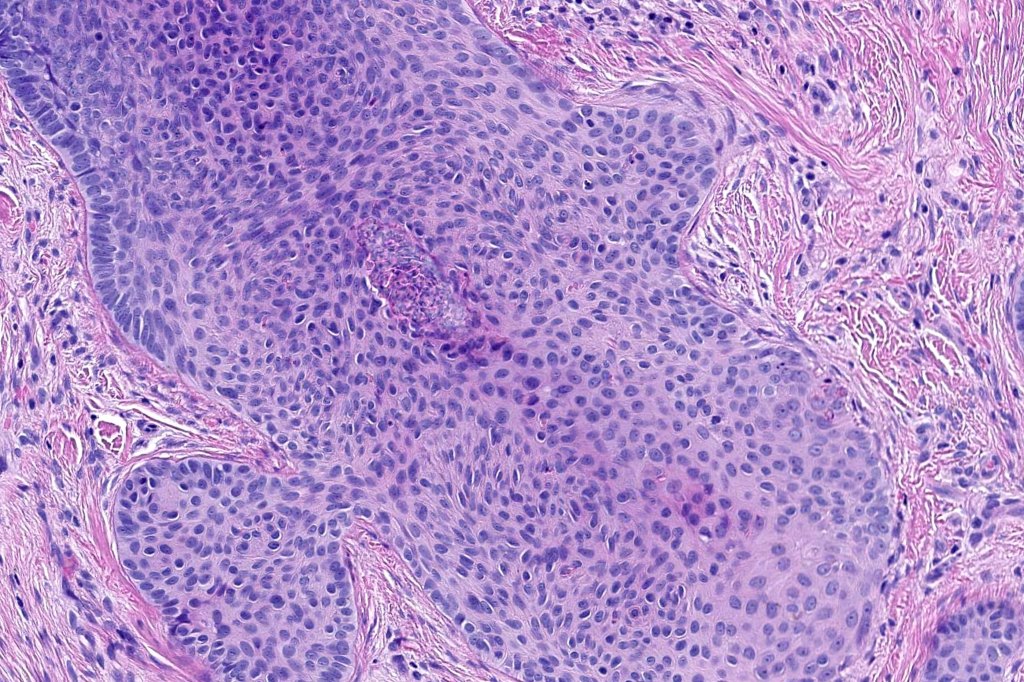

Histological features

•Biphasic tumors comprising germinative epithelial and mesenchymal components

•Uniform basaloid cells with peripheral palisading and often marked mitotic activity

•No pleomorphism

•Stromal component associated with indentation of epithelial component- follicular mesenchymal bodies (uncommon, more often seen in trichoepithelioma)

•Stromal amyloid often present

•Merkel cells are commonly present

•Trichogerminoma (see images)